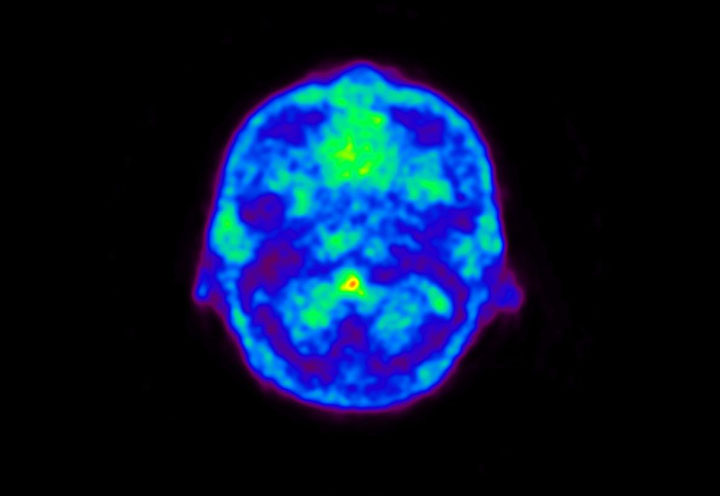

Head / Case5 : Amyloid

Coronal

Courtesy : Kindai University Hospital

- Imaging protocol

- Injected dose: 4.27 MBq/kg, 18F-Flutemetamol

- Uptake time: 99 minutes

- Scan time: 20 minutes